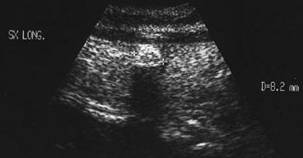

FleGmon aL loJEi tiroidIeNE

Femeie de 56 ani. Supuratie a lojei tiroidiene

stangi care prinde si sternocleidomastoidianul la o pacienta operata in urma cu

8 ani cu lobectomie stanga partiala pentru patologie nodulara benigna.

Imaginea ecografica a lojei laterocervicale stangi. Clinic - tumefactie, durere, disfagie; nodul marcat hipoecogen de 11x19mm, cu nucleu central hiperecogen.